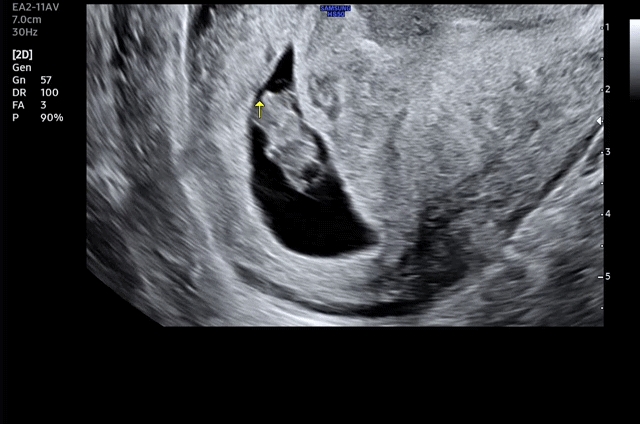

8주 초음파 꼬물이 젤리곰

입덧을 전혀 안하는 저 .. 초음파 보러 가기전까지 시간이 왜이리 더딘지 모르겠어요 🤣 오늘 8주차 젤리곰 보고왔어요 꼬물꼬물 잘 움직이고 있더라구요 !! 이제 아가 보려면 4주 뒤 .......